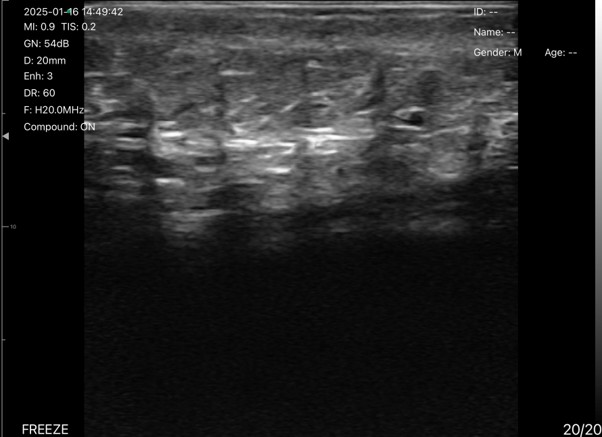

Case: Skin and Subcutaneous Tissue

The images show the skin and subcutaneous tissue in ultrasound mode.